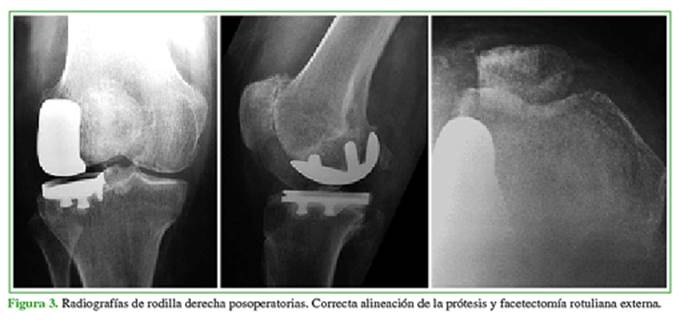

Evaluación radiográfica preoperatoria femorotibial: todos los casos correspondieron al estadio 4 en la clasificación de Kellgren y Lawrence en el compartimento externo; se observaron dos casos de subluxación en el plano coronal. El eje preoperatorio fue de 12,3º ± 4,1º de valgo, se destacaban 10 casos de valgo >15º, entre ellos, tres casos severos de 20º, reductibles en maniobras de varo-valgo forzado. Evaluación radiográfica posoperatoria femorotibial: el eje fue de 5,2º ± 3,1º de valgo (p <0,001) (Figura 3). Se detectó la progresión del proceso degenerativo artrósico en el compartimento medial en un paciente, que desarrolló cambios grado 2 y sintomatología interna.